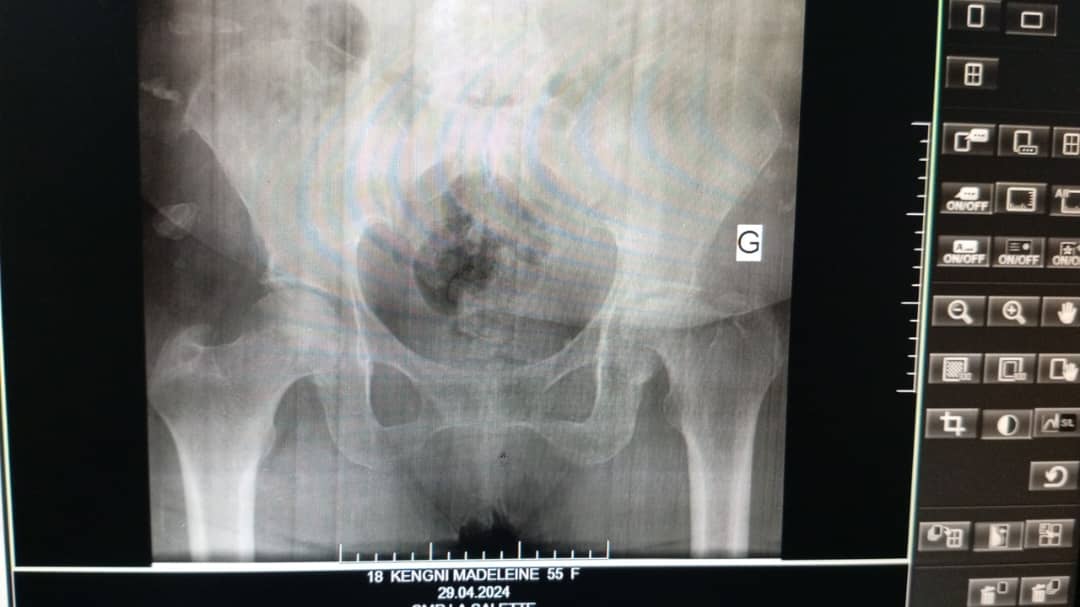

Arthroplastie totale de hanche

L'arthroplastie totale de hanche est une intervention chirurgicale visant à remplacer l'articulation de la hanche par une prothèse.